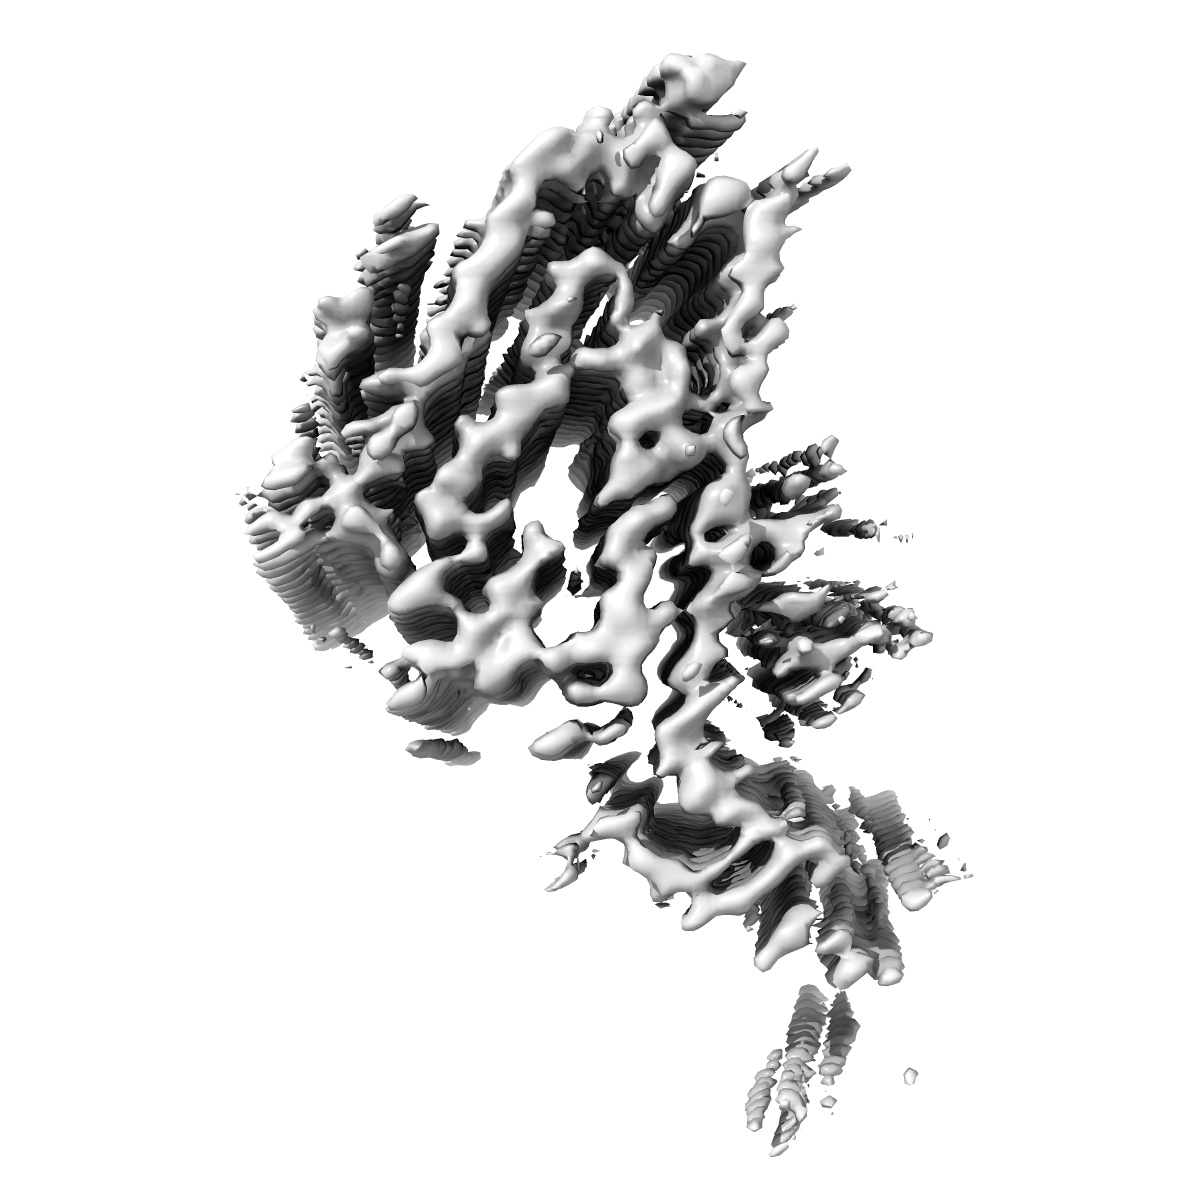

Additional cryo-EM structure of cardiac amyloid AL59 - bent polymorph

EMD-50271

Helical reconstruction3.9 Å